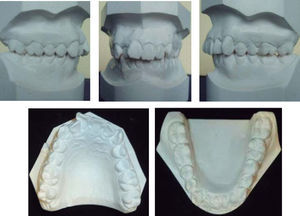

A la exploración clínica extraoral, presenta un patrón simétrico, mesofacial con perfil recto y armonía labial (Figura 1).

El examen intraoral revela que el paciente presenta clase II molar y clase II canina bilateral, apiñamiento moderado anterior superior e inferior, línea media maxilar desviada a la derecha, sobremordida horizontal de 5mm, sobremordida vertical de 3mm, la arcada de forma cuadrada en maxilar, así como la arcada de forma ovalada en mandíbula y los tejidos se observan sanos periodontalmente (Figura 2).

En el análisis de modelos se obtuvo un resultado de discrepancia dental en relación con el espacio disponible de -7mm en maxilar y -3mm en arco mandibular (Figura 4).